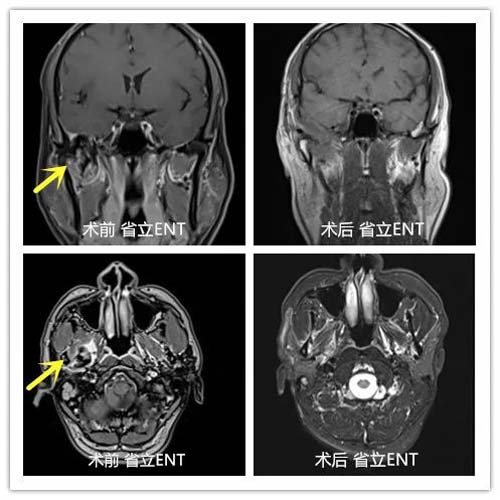

43岁的患者王先生(化名)因右耳反复闷堵听力下降3个月,辗转多家医院未得到明确诊断,遂来我院就诊。经杨会明主治医生、于淑东副主任检查,强化MRI可见王先生右侧颞骨岩部、颅底占位性病变突入颅内,肿物体积大、位置深。

术后8天患者拆线出院,无任何术后并发症,术后MRI增强图像提示瘤体切除彻底,恢复良好。